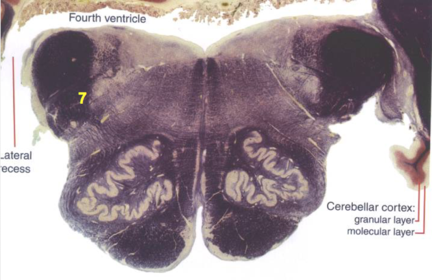

| Trapezoid body | |

| Ventral trigeminothalamic tract | |

| Superior olive | |

| Central tegmental tract | |

| Superior cerebellar peduncle | |

| Dentate nucleus | |

| Fastigial nucleus | |

| Middle cerebellar peduncle | |

| Superior vestibular nucleus | |

| Medial lemniscus | |

| Longitudinal pontine fibers (corticospinal tract) | |

| Transverse pontine fibers (dark fibers) | |

| Pontine nuclei (pale) | |

| Cerebellar vermis | |

| Lateral lemniscus | |

| Medial longitudinal fasciculus | |

| Longitudinal pontine fibers (c-spinal, c-bulbar, c-pontine fibers) | |

| Transverse pontine fibers (dark) | |

| ALS | |